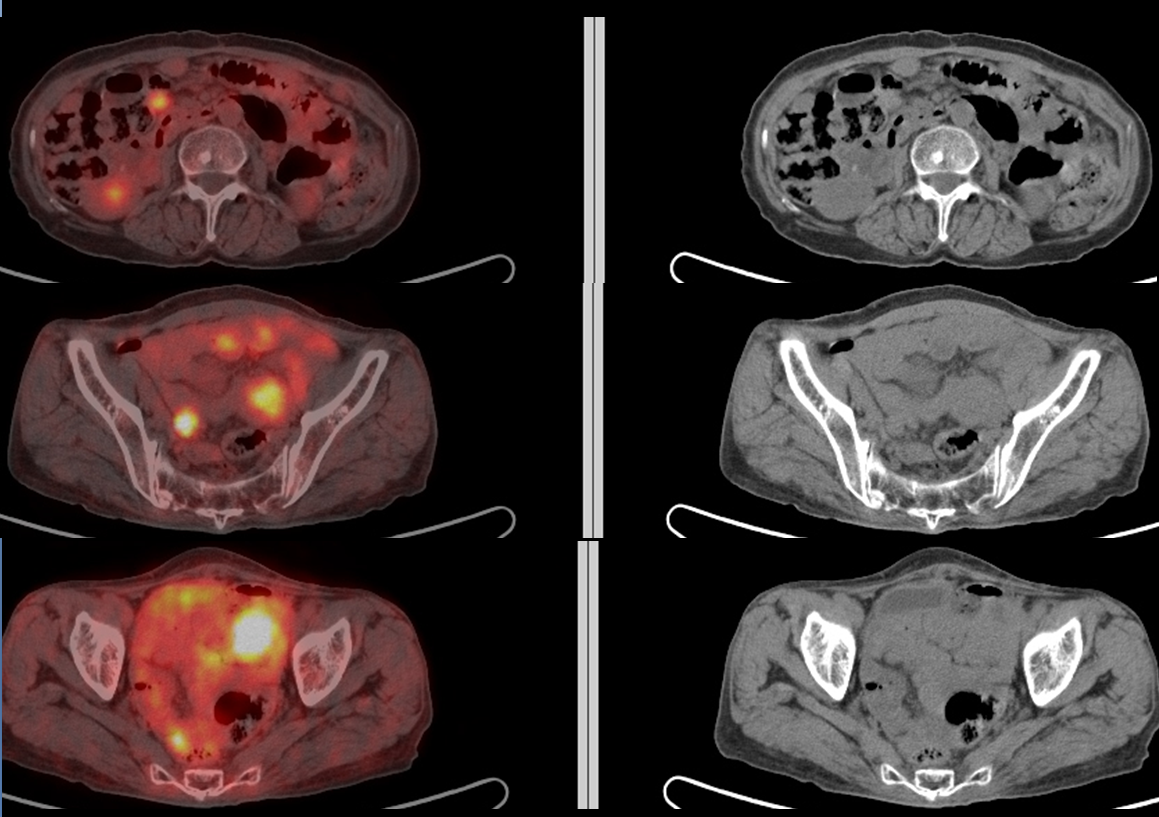

Imaging - Cancer Discovery

Cally reduced omental metastasis of ovarian cancer cells. Collectively, these data provide a rationale for why cancer cells metastasize to a lipid-rich microenvironment that may be applicable to other tumor types, and identify FABP4 as a ... Read Full Source